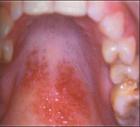

扁平苔藓是一种比较常见的粘膜病,其发病的原因也是比较复杂的。经大量扁平苔藓病历的总结得出,绝大部分的病症的发生与精神情绪存在有一定的关系。

因多种原因的共同作用,导致体内出现紊乱、五脏六腑功能失调而发病。也有的患者病症的发生与牙齿长期不良剌激有关。